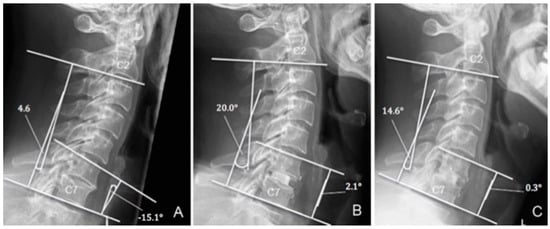

3.2. Radiological Outcomes